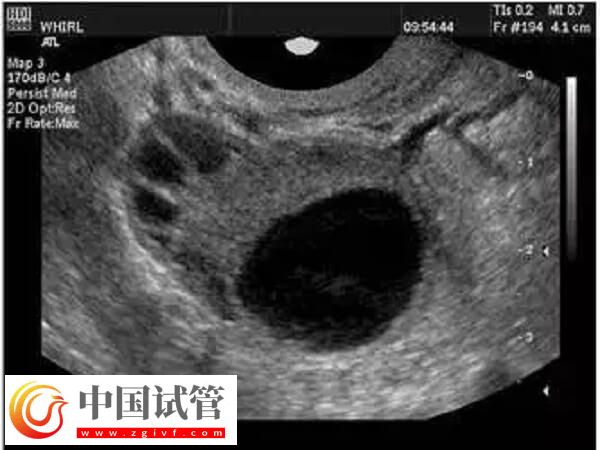

正常情況下,女性每個月只會有一個成熟的卵子形成并排出,然后和精子進行結合。試管嬰兒為了進一步提高成功率,往往都會經(jīng)歷促排卵階段,促使女性卵巢中的多個卵泡同時發(fā)育成熟,然后進行取卵,取卵的數(shù)量和質(zhì)量關系到試管的成功率。下面給大家分析一下取卵出現(xiàn)異形卵子的原因:

病理因素也可能導致卵子形態(tài)異常,如果女性患有異位妊娠、子宮內(nèi)膜異位癥、子宮肌瘤、卵巢囊腫、卵巢結核等疾病,都有可能出現(xiàn)異形卵子。